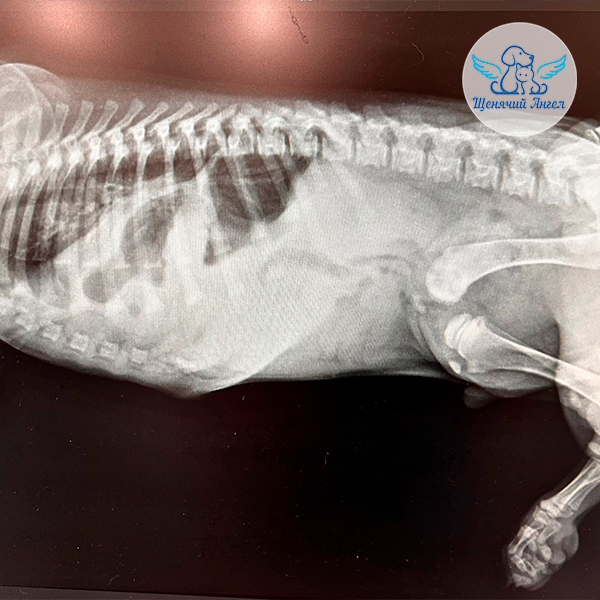

По результатам диагностики 🩻 у Амиго обнаружены травмы грудной и тазовой конечностей 🐾 (перелом костей предплечья и бедренной кости слева), а также возникло подозрение на диафрагмальную грыжу – опасное состояние, при котором органы брюшной полости могут смещаться в грудную полость и нарушать дыхание 😢.

В клинике «Зоовет» 🏥 диагнозы подтвердились, и врачи приняли решение о незамедлительном хирургическом вмешательстве: Амиго сразу прооперировали диафрагмальную грыжу, вернув органы на свои места и восстановив целостность диафрагмы ❤️‍🩹.

После стабилизации состояния Амиго осмотрел врач-ортопед 👨🏻‍⚕️. Он подтвердил необходимость фиксации переломов, причём с учётом его возраста и состояния – сразу двух. Это даст малышу шанс быстрее встать на лапки и избежать осложнений 🙏🏻.

В клинике «Сколково Вет» хирург Горшков С.С. провёл Амиго остеосинтез костей предплечья и бедренной кости – установку металлических конструкций 🔩, которые фиксируют кости и позволяют им правильно срастаться.